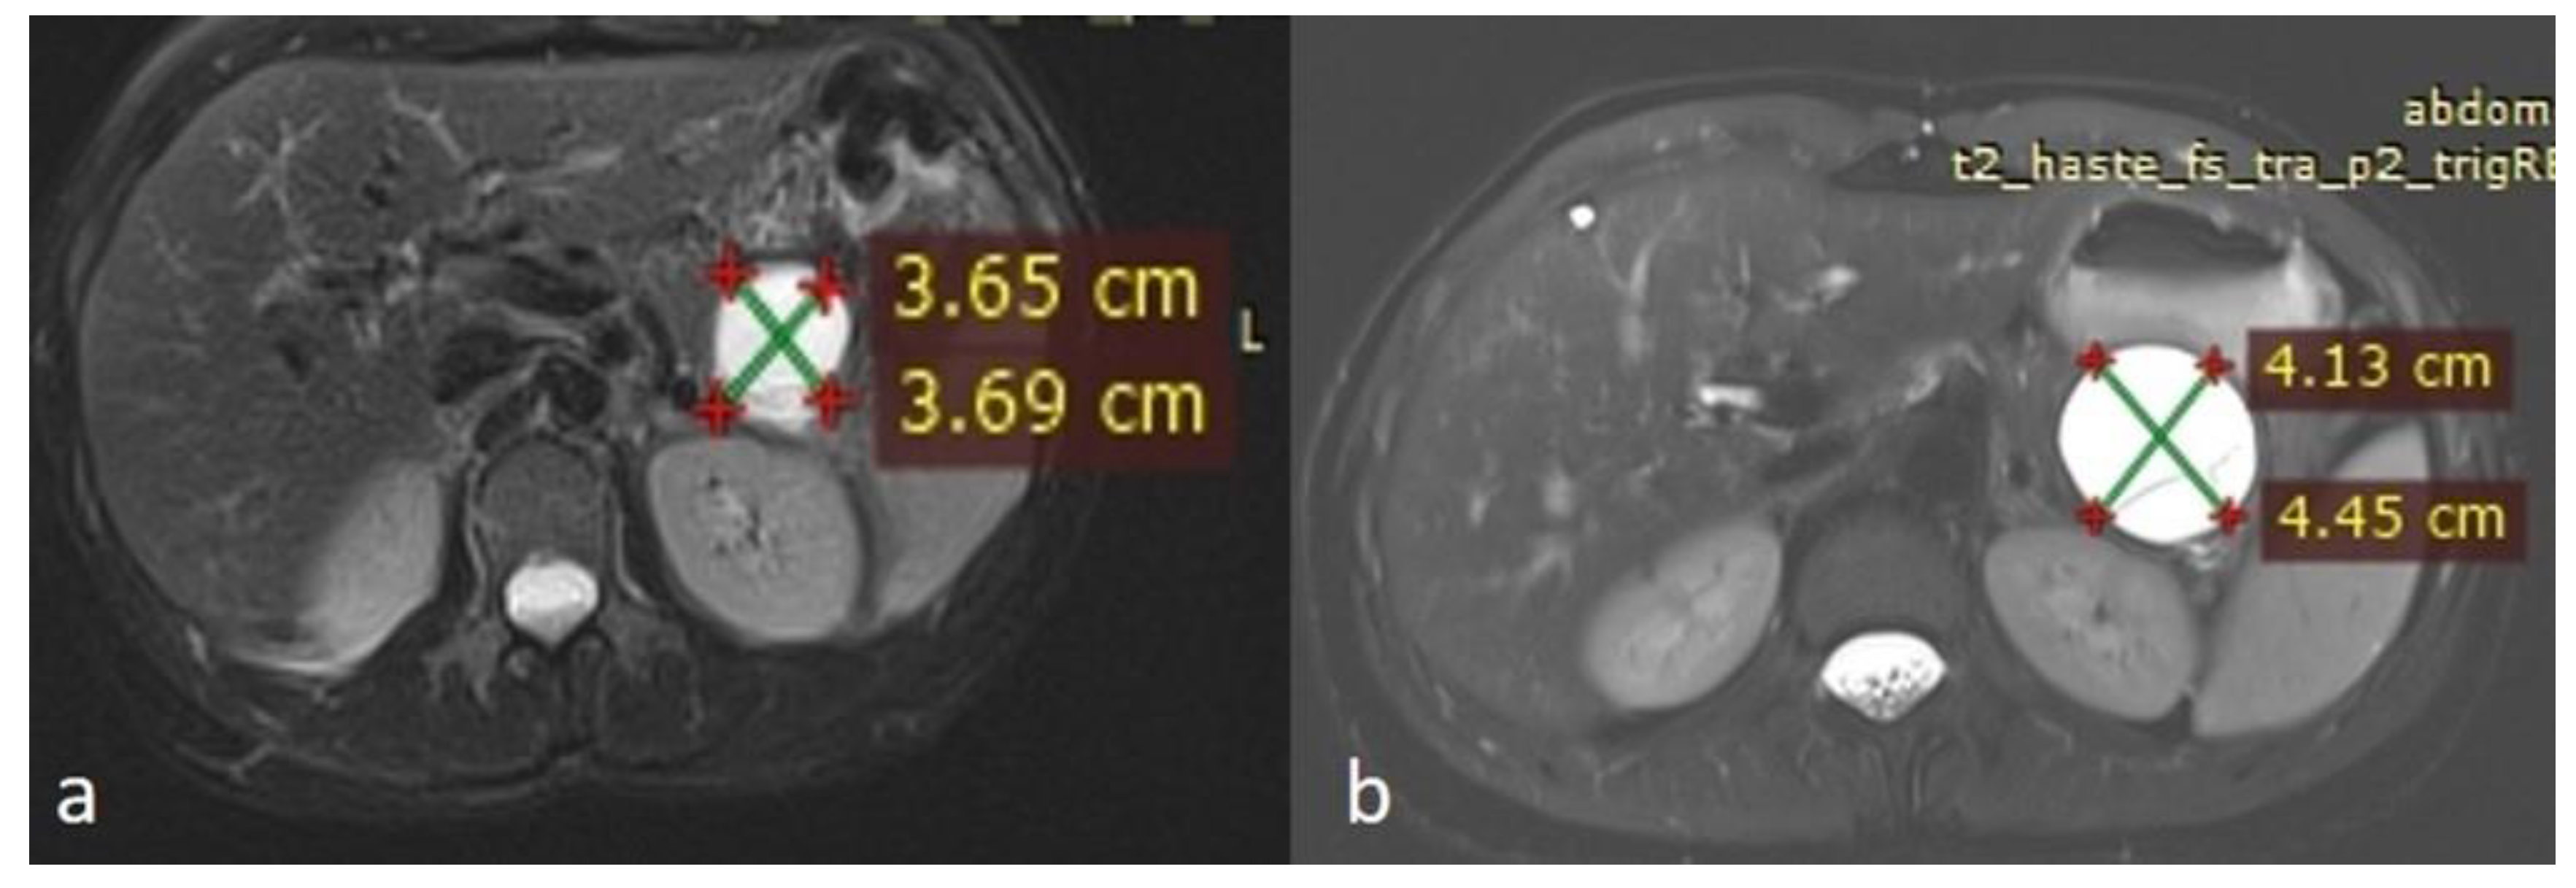

An MRI performed one year after the initial imaging and two months before admission revealed an increase in the size of the pancreatic cystic lesion to 4.5 cm (Figure 3 and Figure 4) with enhancement of its thin wall and internal septa, confirming its progressive nature. The lesion continued to compress the pancreatic tail and the greater curvature of the stomach, without causing pancreatic duct dilation. The imaging also showed low signal intensity on T1- and high signal intensity on T2-weighted sequences, with capsule enhancement post-contrast, suggesting a mucinous cystic neoplasm (Figure 4). Additionally, the MRI confirmed the presence of a 9 mm hemangioma and a small liver cyst, both unchanged from prior scans. No enlarged retroperitoneal lymph nodes were observed, and the MRCP findings showed normal intrahepatic bile ducts, common hepatic bile duct, gallbladder, and pancreatic duct. No abnormalities were found in the spleen, kidneys, or adrenal glands.

Figure 3.

(a,b) Axial sequences of the upper abdomen comparison showed an increase in the lesion size.